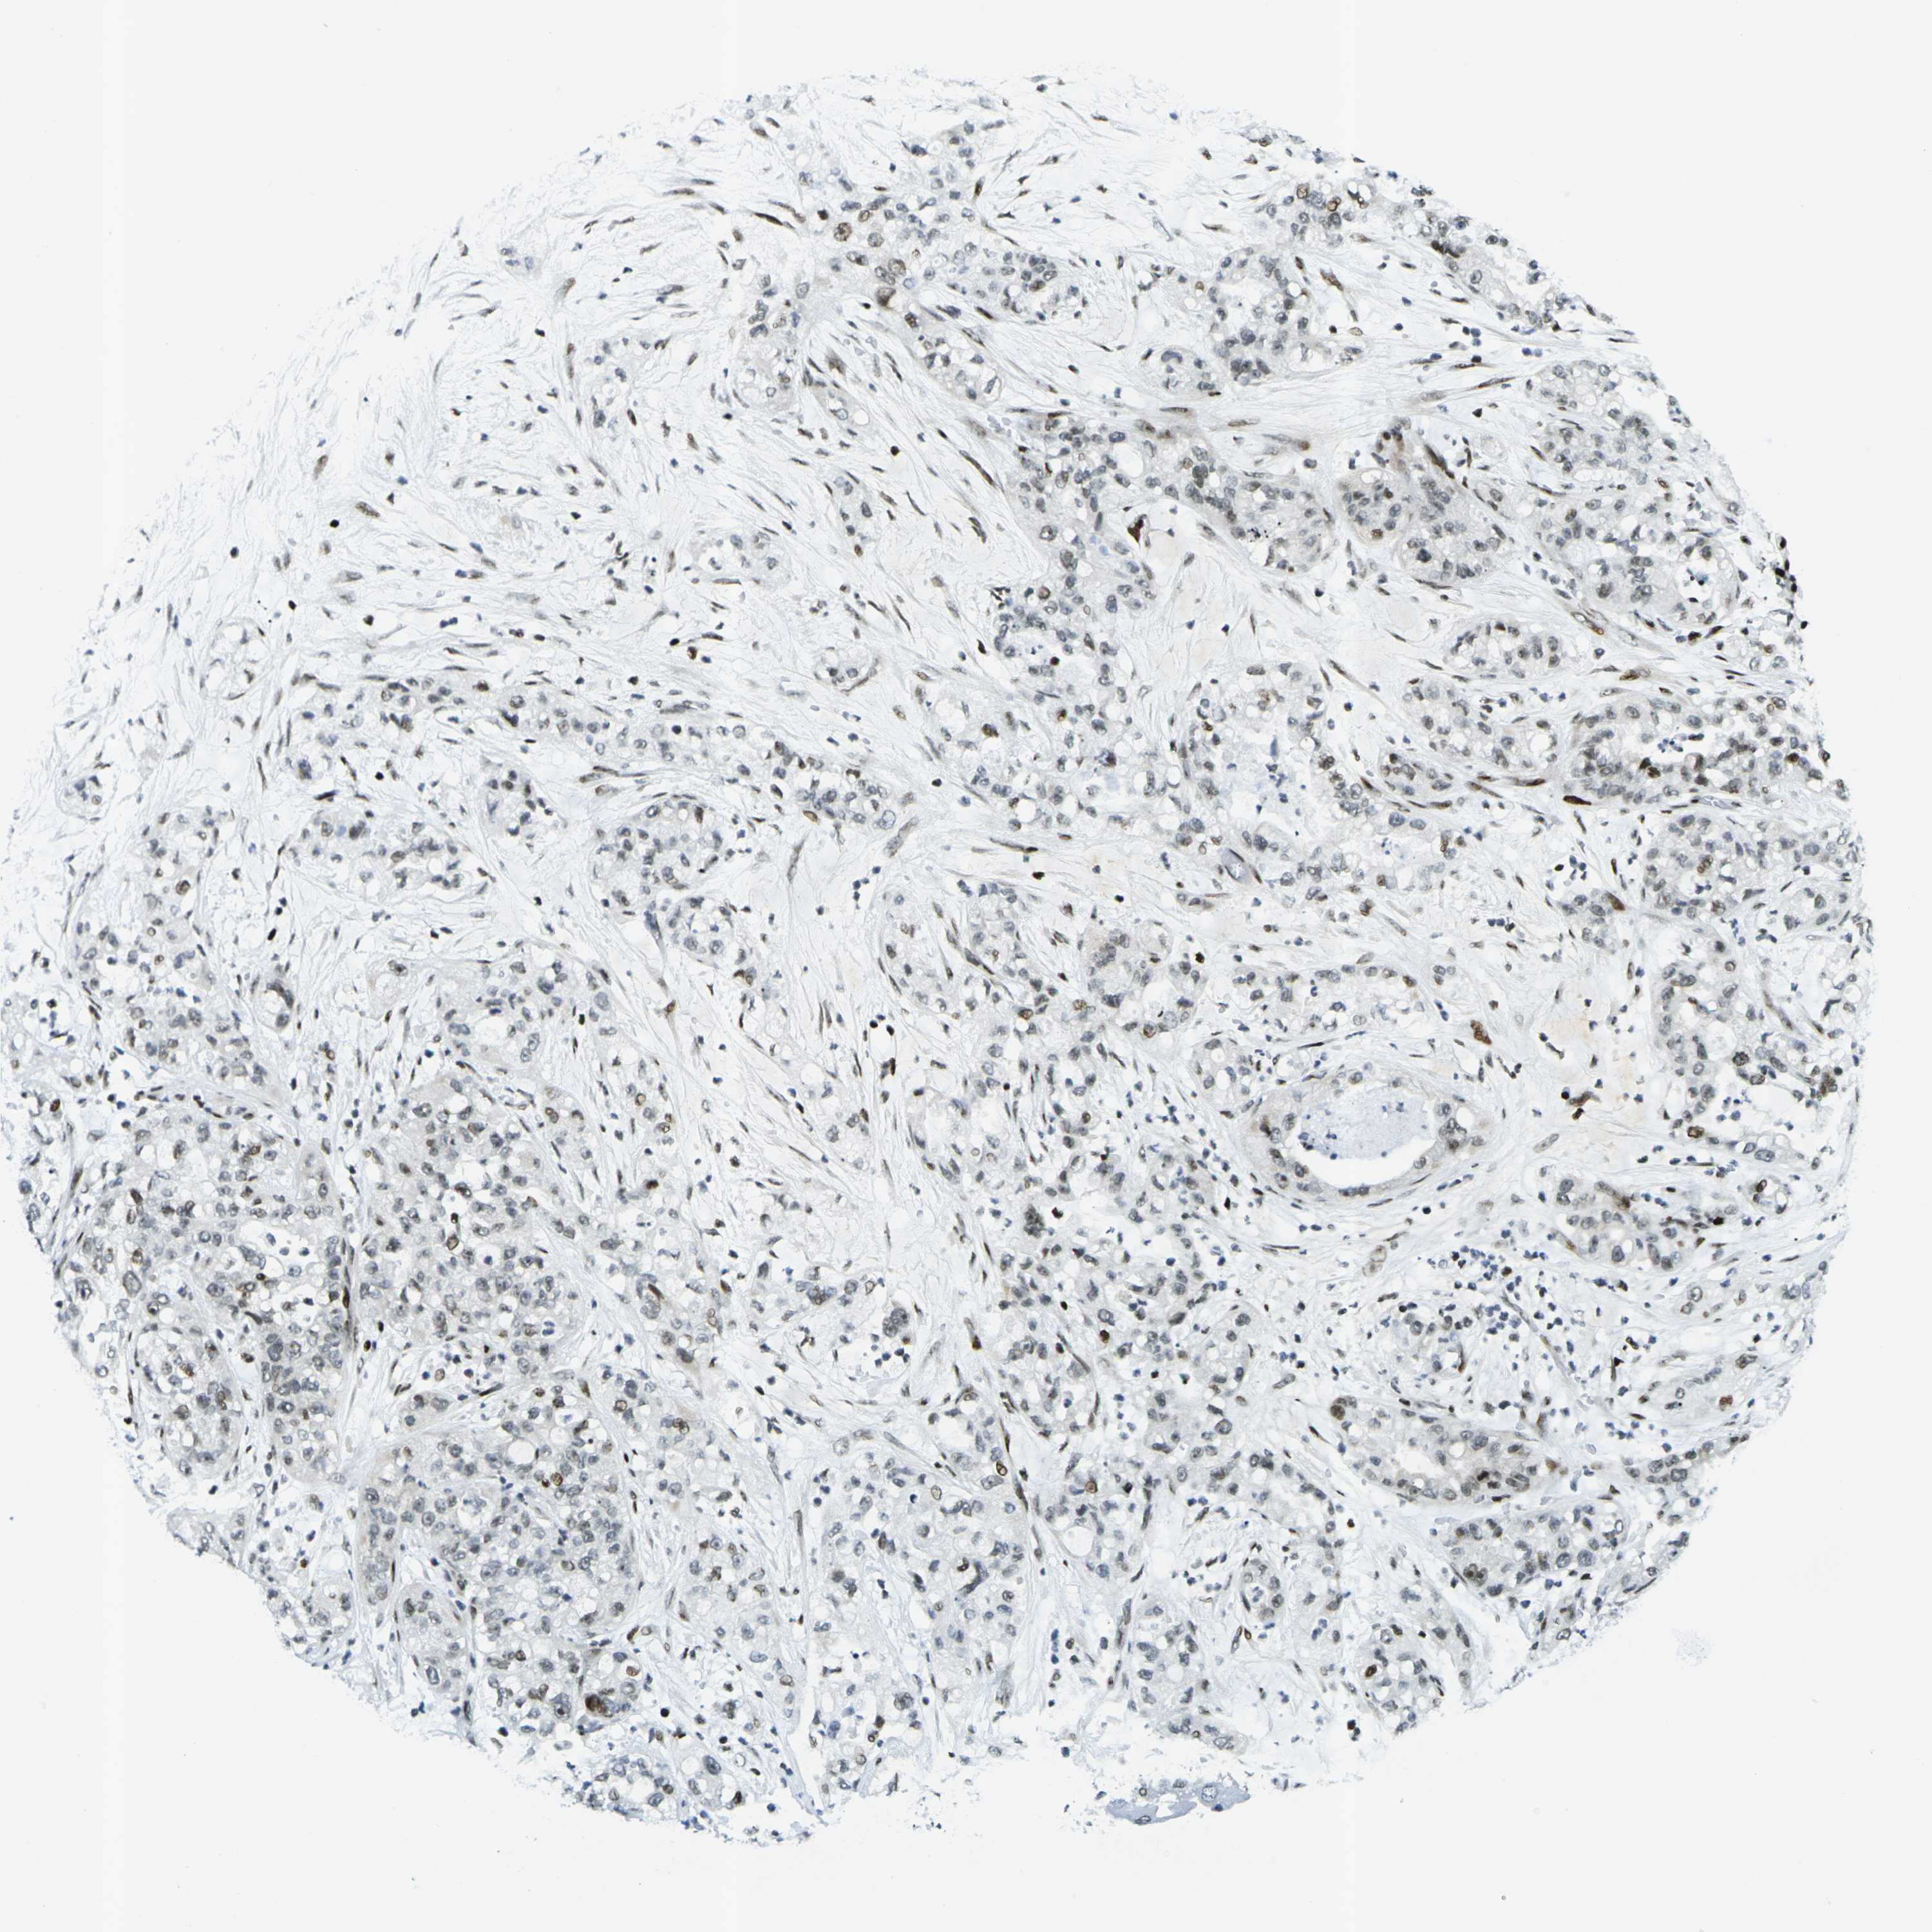

PANCREATIC CANCER - Protein expressioni

A mouse-over function shows sample information and annotation data. Click on an image to view it in a full screen mode. Samples can be filtered based on level of antibody staining by selecting one or several of the following categories: high, medium, low and not detected. The assay and annotation is described here.

Note that samples used for immunohistochemistry by the Human Protein Atlas do not correspond to samples in the TCGA dataset.

Antibody stainingi

Antibody staining in the annotated cell types in the current human tissue is reported as not detected, low, medium, or high, based on conventional immunohistochemistry profiling in selected tissues. This score is based on the combination of the staining intensity and fraction of stained cells.

Each image is clickable and will lead to virtual microscopy that enables deeper exploration of all samples and also displays staining intensity scores, fraction scores and subcellular localization as well as patient and tissue information for each sample.

Antibody HPA042570

Adenocarcinoma, NOS